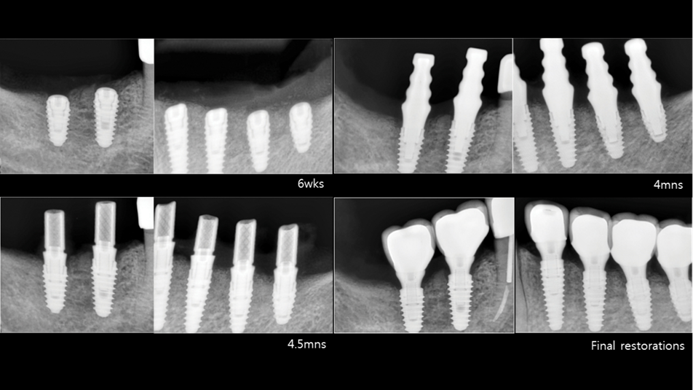

Clinical case: Delayed implant placement: sinus floor elevation by means of lateral

approach & implant placement with GBR

- Courtesy of Dr. Irfan Abas, Netherlands -